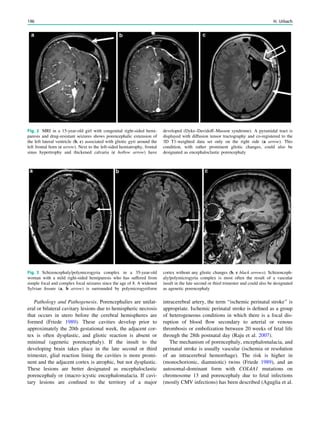

• 74.

focal epilepsy arerendered seizure-free after epilepsy sur- gery, and have a worse prognosis compared with patients with refractory focal epilepsy and an epileptic lesion on MRI (Lee et al. 2005). 4.4.1 Ictal SPECT In MRI-negative refractory focal epilepsy, reevaluation of the MRI, guided by the ictal SPECT, reveals small focal dys- plastic lesions in around 15% of cases (Van Paesschen et al. 2007a; Van Paesschen and Ictal 2004) (Fig. 6). SISCOM can be used to guide placement of intracranial electrodes (Ahnlide et al. 2007). SISCOM may alter and extend the strategy for electrode placement in invasive recording. Favorable surgical outcome has been observed when intra- cranial EEG was concordant with SISCOM hyperperfusion. SISCOM localization, therefore, is an independent method with an impact in patients with refractory partial epilepsy scheduled for intracranial EEG studies. In comparison with MRI, FDG-PET, magnetoencephalography, and scalp EEG, ictal SPECT is probably the most sensitive technique to localize the ictal onset zone in extratemporal lobe epilepsy, and to predict a seizure-free outcome after epilepsy surgery (Knowlton et al. 2008; Kim et al. 2009). 4.4.2 2-[18 F]Fluoro-2-deoxy-D-glucose PET FDG-PET may be useful in MRI-negative temporal lobe epilepsy. Good surgical results have been reported in patients with MRI-negative refractory temporal lobe epi- lepsy and unilateral temporal hypometabolism (Fig. 4). MRI-negative, PET-positive temporal lobe epilepsy may represent a surgically remediable syndrome distinct from mesial temporal lobe epilepsy, with focal hypometabolism involving primarily lateral neocortical rather than mesial temporal structures (Lee et al. 2005; Carne et al. 2004). FDG-PET is most useful in patients with temporal lobe epilepsy when MRI findings are normal or when MRI does not show unilateral temporal lobe abnormalities, and when ictal EEG results are not concordant with MRI findings or seizure symptoms (Uijl et al. 2007). 5 Conclusion Ictal SPECT and FDG-PET are functional nuclear imaging modalities which may provide additional information in the noninvasive presurgical evaluation of patients with refrac- tory focal epilepsy when MRI shows a malformation of cortical development (Dupont et al. 2006), dual pathology, or MRI-negative cases, or when the data from the presur- gical evaluation are discordant. Both may facilitate the detection of a subtle focal dysplastic lesion when the MRI findings were initially reported as normal, and may allow epilepsy surgery after a noninvasive presurgical evaluation. Ictal SPECT may guide placement of electrodes and grids for invasive EEG studies. Ictal SPECT and FDG-PET can be integrated in a multimodal image, including MRI, trac- tography, EEG–functional MRI and magnetoencephalog- raphy, allowing accurate surgical planning. Both FDG-PET and ictal SPECT can predict seizure-free outcome after epilepsy surgery (Knowlton et al. 2008). References Ahnlide JA, Rosen I, Linden-Mickelsson TP, Kallen K (2007) Does SISCOM contribute to favorable seizure outcome after epilepsy surgery? Epilepsia 48:579–588 Barkovich AJ, Kuzniecky RI, Jackson GD, Guerrini R, Dobyns WB (2005) A developmental and genetic classification for malforma- tions of cortical development. Neurology 27(65):1873–1887 Blümcke I, Thom M, Aronica E et al (2011) The clinicopathologic spectrum of focal cortical dysplasias: a consensus classification proposed by an ad hoc task force of the ILAE Diagnostic Methods Commission. Epilepsia 52:158–174 Blumenfeld H, McNally KA, Vanderhill SD et al (2004) Positive and negative network correlations in temporal lobe epilepsy. Cereb Cortex 14:892–902 Burneo JG, Faught E, Knowlton RC et al (2003) Temporal lobectomy in congenital porencephaly associated with hippocampal sclerosis. Arch Neurol 60:830–834 Carne RP, O’Brien TJ, Kilpatrick CJ et al (2004) MRI-negative PET- positive temporal lobe epilepsy: a distinct surgically remediable syndrome. Brain 127:2276–2285 Cendes F, Cook MJ, Watson C et al (1995) Frequency and characteristics of dual pathology in patients with lesional epilepsy. Neurology 45:2058–2064 Chang EF, Wang DD, Barkovich AJ et al (2011) Predictors of seizure freedom after surgery for malformations of cortical development. Ann Neurol 70:151–162 Chassagnon S, Namer IJ, Armspach JP et al (2009) SPM analysis of ictal-interictal SPECT in mesial temporal lobe epilepsy: relation- ships between ictal semiology and perfusion changes. Epilepsy Res 85:252–260 Chassoux F, Rodrigo S, Semah F et al (2010) FDG-PET improves surgical outcome in negative MRI Taylor-type focal cortical dysplasias. Neurology 14(75):2168–2175 Cho JW, Hong SB, Lee JH et al (2010) Contralateral hyperperfusion and ipsilateral hypoperfusion by ictal SPECT in patients with mesial temporal lobe epilepsy. Epilepsy Res 88:247–254 Diehl B, LaPresto E, Najm I et al (2003) Neocortical temporal FDG- PET hypometabolism correlates with temporal lobe atrophy in hippocampal sclerosis associated with microscopic cortical dys- plasia. Epilepsia 44:559–564 Duncan JS (2010) Imaging in the surgical treatment of epilepsy. Nat Rev Neurol 6:537–550 Dupont P, Van Paesschen W, Palmini A et al (2006) Ictal perfusion patterns associated with single MRI-visible focal dysplastic lesions: implications for the noninvasive delineation of the epileptogenic zone. Epilepsia 47:1550–1557 Goffin K, Dedeurwaerdere S, Van Laere KJ, Van Paesschen W (2008) Neuronuclear assessment of patients with epilepsy. Semin Nucl Med 38:227–239 Goffin K, Van Paesschen W, Dupont P et al (2010) Anatomy-based reconstruction of FDG-PET images with implicit partial volume correction improves detection of hypometabolic regions in patients 70 W. Van Paesschen et al.

• 75.

with epilepsy dueto focal cortical dysplasia diagnosed on MRI. Eur J Nucl Med Mol Imaging 37:1148–1155 Henry TR, Mazziotta JC, Engel J Jr et al (1990) Quantifying interictal metabolic activity in human temporal lobe epilepsy. J Cereb Blood Flow Metab 10:748–757 Henry TR, Mazziotta JC, Engel J Jr (1993) Interictal metabolic anatomy of mesial temporal lobe epilepsy. Arch Neurol 50:582–589 Jokeit H, Seitz RJ, Markowitsch HJ, Neumann N, Witte OW, Ebner A (1997) Prefrontal asymmetric interictal glucose hypometabolism and cognitive impairment in patients with temporal lobe epilepsy. Brain 120(Pt 12):2283–2294 Kapucu OL, Nobili F, Varrone A et al (2009) EANM procedure guideline for brain perfusion SPECT using 99mTc-labelled radiopharmaceuti- cals, version 2. Eur J Nucl Med Mol Imaging 36:2093–2102 Kim JH, Im KC, Kim JS et al (2007) Ictal hyperperfusion patterns in relation to ictal scalp EEG patterns in patients with unilateral hippocampal sclerosis: a SPECT study. Epilepsia 48:270–277 Kim JT, Bai SJ, Choi KO et al (2009) Comparison of various imaging modalities in localization of epileptogenic lesion using epilepsy surgery outcome in pediatric patients. Seizure 18:504–510 Kim YH, Kang HC, Kim DS et al (2011) Neuroimaging in identifying focal cortical dysplasia and prognostic factors in pediatric and adolescent epilepsy surgery. Epilepsia 52:722–727 Knowlton RC, Elgavish RA, Bartolucci A et al (2008) Functional imaging: II. Prediction of epilepsy surgery outcome. Ann Neurol 64:35–41 Lee SK, Lee DS, Yeo JS et al (2002) FDG-PET images quantified by probabilistic atlas of brain and surgical prognosis of temporal lobe epilepsy. Epilepsia 43:1032–1038 Lee SK, Lee SY, Kim KK, Hong KS, Lee DS, Chung CK (2005) Surgical outcome and prognostic factors of cryptogenic neocortical epilepsy. Ann Neurol 58:525–532 Li LM, Fish DR, Sisodiya SM, Shorvon SD, Alsanjari N, Stevens JM (1995) High resolution magnetic resonance imaging in adults with partial or secondary generalised epilepsy attending a tertiary referral unit. J Neurol Neurosurg Psychiatry 59:384–387 Li LM, Cendes F, Andermann F et al (1999) Surgical outcome in patients with epilepsy and dual pathology. Brain 122(Pt 5):799–805 Lüders H, Schuele SU (2006) Epilepsy surgery in patients with malformationsofcorticaldevelopment.CurrOpinNeurol19:169–174 Marusic P, Najm IM, Ying Z et al (2002) Focal cortical dysplasias in eloquent cortex: functional characteristics and correlation with MRI and histopathologic changes. Epilepsia 43:27–32 Nelissen N, Van Paesschen W, Baete K et al (2006) Correlations of interictal FDG-PET metabolism and ictal SPECT perfusion changes in human temporal lobe epilepsy with hippocampal sclerosis. Neuroimage 15(32):684–695 O’Brien TJ, So EL, Mullan BP et al (1998) Subtraction ictal SPECT co-registered to MRI improves clinical usefulness of SPECT in localizing the surgical seizure focus. Neurology 50:445–454 O’Brien TJ, So EL, Mullan BP et al (2000) Subtraction peri-ictal SPECT is predictive of extratemporal epilepsy surgery outcome. Neurology 12(55):1668–1677 O’Brien TJ, So EL, Cascino GD et al (2004) Subtraction SPECT coregistered to MRI in focal malformations of cortical develop- ment: localization of the epileptogenic zone in epilepsy surgery candidates. Epilepsia 45:367–376 Palmini A, Najm I, Avanzini G et al (2004) Terminology and classification of the cortical dysplasias. Neurology 23(62):S2–S8 Rosenow F, Lüders H (2001) Presurgical evaluation of epilepsy. Brain 124:1683–1700 Salamon N, Kung J, Shaw SJ et al (2008) FDG-PET/MRI coregistra- tion improves detection of cortical dysplasia in patients with epilepsy. Neurology 11(71):1594–1601 Savic I, Altshuler L, Baxter L, Engel J Jr (1997) Pattern of interictal hypometabolism in PET scans with fludeoxyglucose F 18 reflects prior seizure types in patients with mesial temporal lobe seizures. Arch Neurol 54:129–136 Takaya S, Hanakawa T, Hashikawa K et al (2006) Prefrontal hypofunction in patients with intractable mesial temporal lobe epilepsy. Neurology 14(67):1674–1676 Uijl SG, Leijten FS, Arends JB, Parra J, van Huffelen AC, Moons KG (2007) The added value of [18F]-fluoro-D-deoxyglucose positron emission tomography in screening for temporal lobe epilepsy surgery. Epilepsia 48:2121–2129 Valenti MP, Froelich S, Armspach JP et al (2002) Contribution of SISCOM imaging in the presurgical evaluation of temporal lobe epilepsy related to dysembryoplastic neuroepithelial tumors. Epi- lepsia 43:270–276 Van Paesschen W (2004) Ictal SPECT. Epilepsia 45(Suppl 4): 35–40 Van Paesschen W, Dupont P, Van Heerden B et al (2000) Self- injection ictal SPECT during partial seizures. Neurology 23(54): 1994–1997 Van Paesschen W, Dupont P, Van Driel G, Van Billoen H, Maes A (2003) SPECT perfusion changes during complex partial seizures in patients with hippocampal sclerosis. Brain 126:1103–1111 Van Paesschen W, Dupont P, Sunaert S, Goffin K, Van Laere KJ (2007a) The use of SPECT and PET in routine clinical practice in epilepsy. Curr Opin Neurol 20:194–202 Van Paesschen W, Porke K, Fannes K et al (2007b) Cognitive deficits during status epilepticus and time course of recovery: a case report. Epilepsia 48:1979–1983 Varghese GI, Purcaro MJ, Motelow JE et al (2009) Clinical use of ictal SPECT in secondarily generalized tonic-clonic seizures. Brain 132:2102–2113 Wu JY, Salamon N, Kirsch HE et al (2010) Noninvasive testing, early surgery, and seizure freedom in tuberous sclerosis complex. Neurology 2(74):392–398 SPECT and PET 71

• 76.